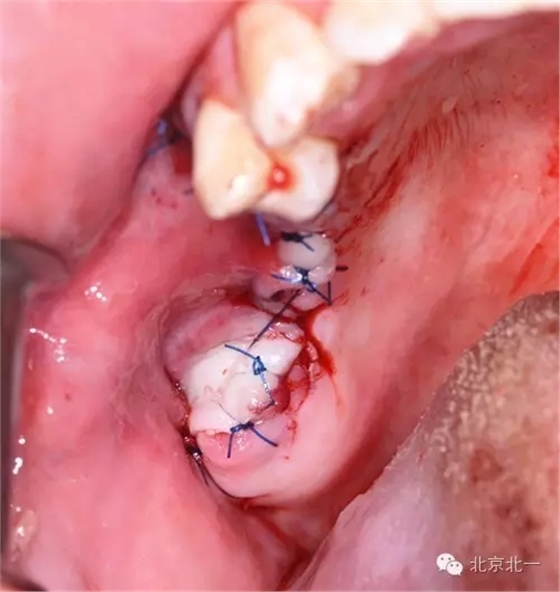

圖五:手術區(qū)可見拔牙窩

圖十:縫合。

圖十七:縫合。非潛入